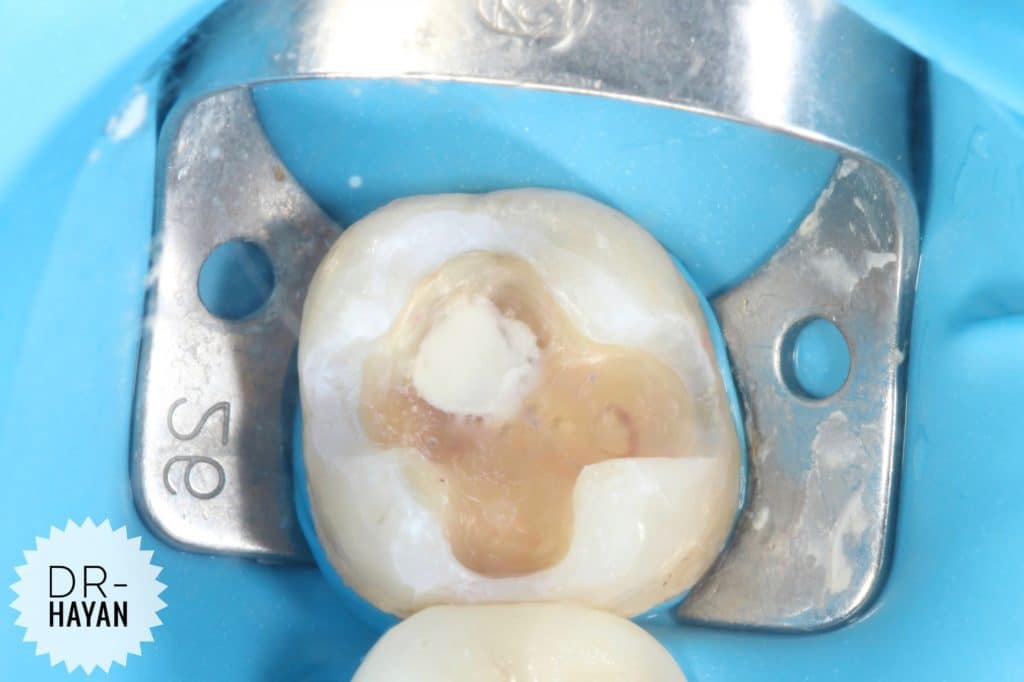

Bonding process

Enamel soo easy

But the dentine it’s challenging

Bonding

, universal bond

2 layer

Bond 👉🏻 rubbing 20 s remove excess 👉🏻 some air 👉🏻 light cure 20 s

Another one

Then ,

O.5 mm of RESIN COATING on dentin

One layer of universal bond it’s very weak And thickness of one layer about 10 micron

When application 2 layer - we elevated the thickness of adhesive layer to 20 micron

Still it’s weak point in universal bond

Wait 5 minutes and then start working with Compsite

To conversion all the monomer in bonding system

Decouple with time. This protocol states that polymerization shrinkage stress to the developing dentin bond of the hybrid layer should be minimized for a certain period of time (ie 5 to 30 minutes) by keeping initial increments to a minimum thickness